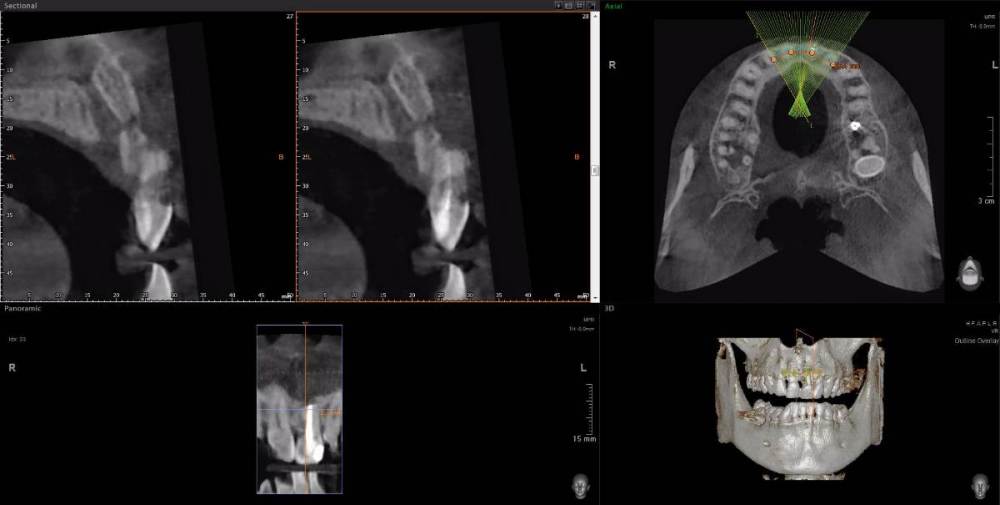

Денис 1 Опубликовано 1 июля, 2021 Поделиться Опубликовано 1 июля, 2021 Здравствуйте. Проблема с передним верхним резцом, кариес под десной. Прошу прокомментировать по КТ https://disk.yandex.ru/d/jRQy8r-N66_CQg возможно ли сохранение зуба в таком состоянии? Я извиняюсь что сразу весь образ диска предоставляю, но у меня на компьютер просмотрщик с диска устанавливаться не хочет. Открыл файлы Фотошопом, но там не понятно ничего. Очень не хочется лишиться переднего зуба, по этому пытаюсь разобраться, существует ли технология лечения зуба с поражением корня под десной? Заранее спасибо за участие. Ссылка на комментарий

wladdX Опубликовано 2 июля, 2021 Поделиться Опубликовано 2 июля, 2021 (изменено) На мой взгляд зуб 21 придётся удалять Изменено 2 июля, 2021 пользователем wladdX 2 Ссылка на комментарий

wladdX Опубликовано 3 июля, 2021 Поделиться Опубликовано 3 июля, 2021 Ни малейших Ссылка на комментарий